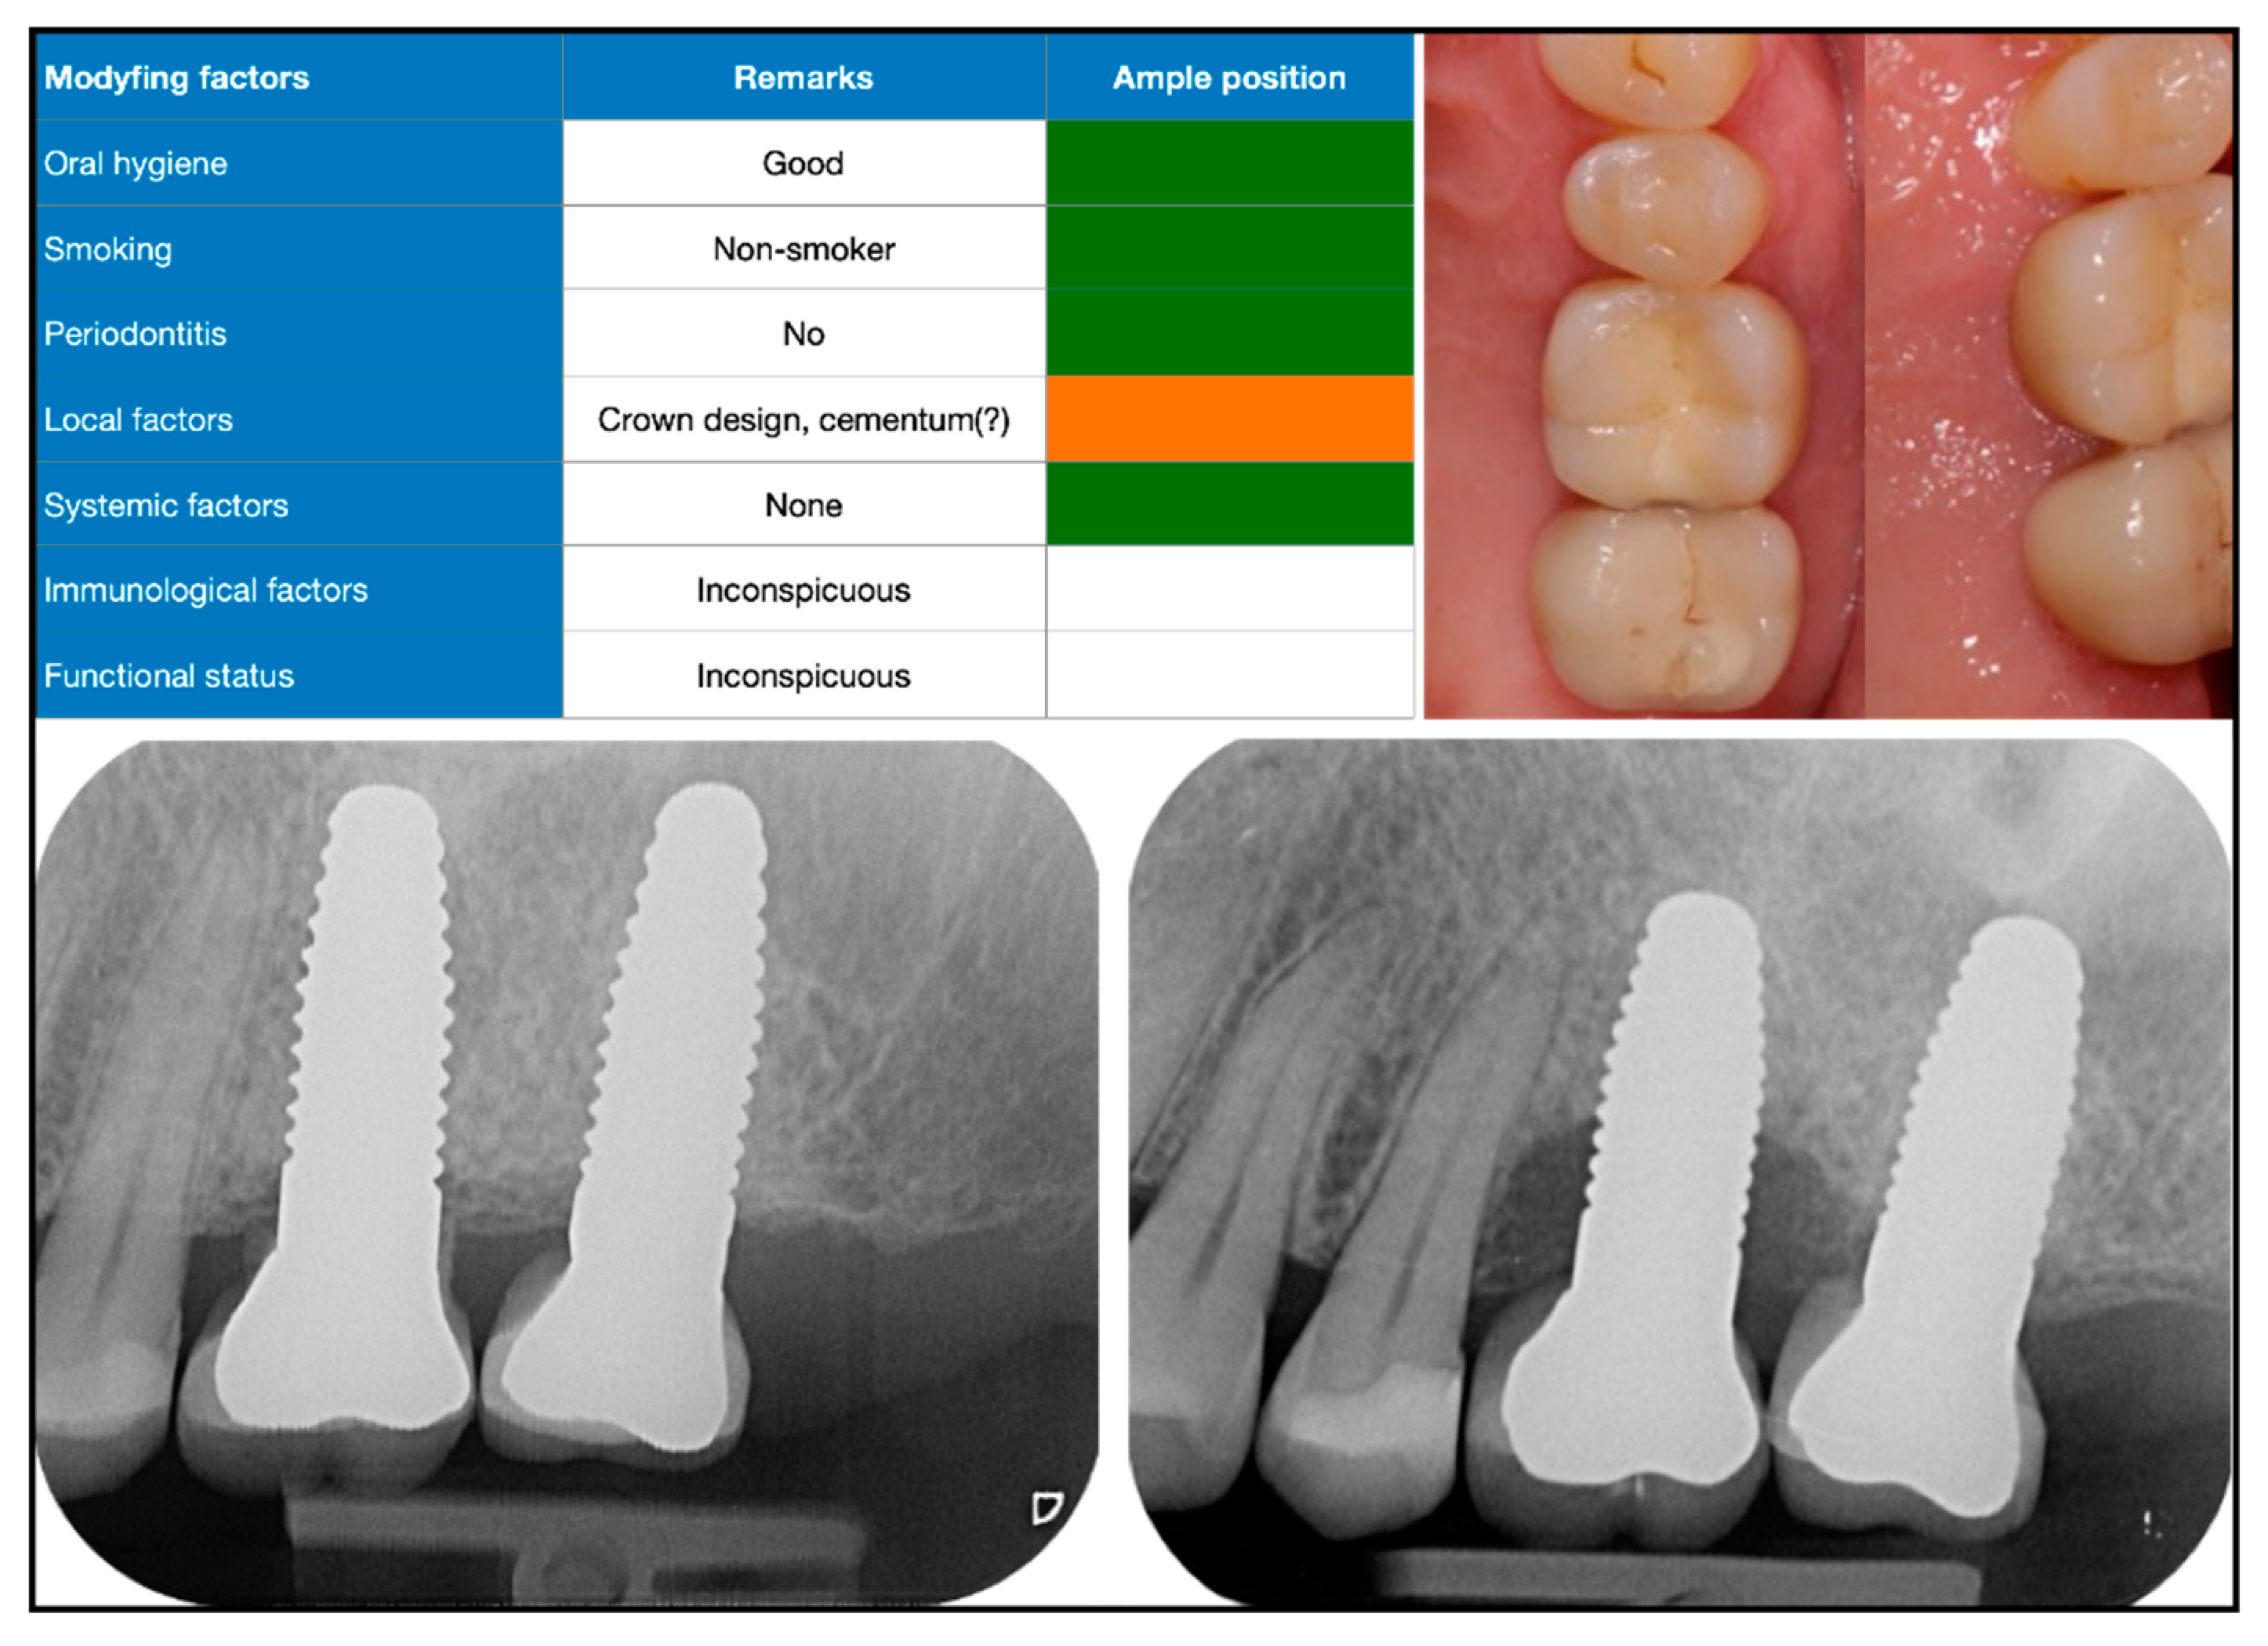

| Local factors (LFs) | Number of patients (%) |

| Present | 87 (46) |

| Absent | 93 (49) |

| NA | 10 (5) |

| Interface between crown and implant on radiograph | Number of patients (%) |

| Gap-free | 86 (45) |

| Insufficient | 100 (53) |

| NA | 4 (2) |